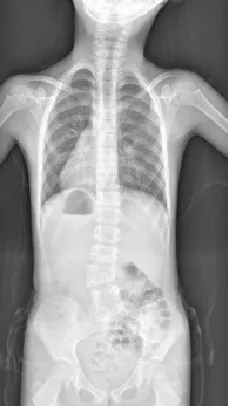

▷早发性脊柱侧凸

早发性脊柱侧凸(EOS),指10岁之前因各种原因导致的脊柱侧凸畸形,如婴幼儿特发性脊柱侧弯、先天性脊柱侧凸、神经肌源性脊柱侧凸等。

▲ 男,14岁,早发性脊柱侧弯、先天性脊柱畸形